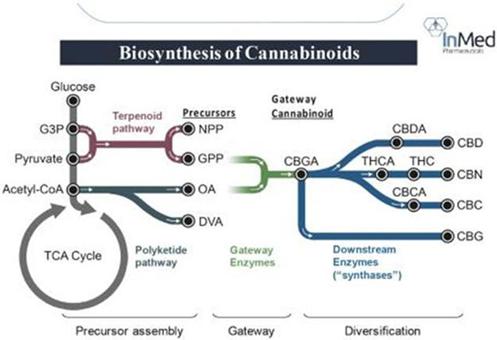

Cannabinoids are prenylated polyketides that are derived from fatty acid and terpenoid precursors. The biosynthesis of these molecules involves four metabolic pathways, two of which originate from central carbon metabolism. The first pathway (the Terpenoid pathway referenced in Figure 1 below) culminates with the synthesis of geranyl pyrophosphate, or “GPP”, and neryl pyrophosphate, or “NPP”. These molecules are terpenoid building blocks, or precursors. The second cannabinoid biosynthetic pathway, or the Polyketide pathway, is a truncated version of a polyketide biosynthetic pathway and results in the second requisite precursor, either: olivetolic acid, or “OA”, and/or divarinic acid, or “DVA”. The polyketide precursors subsequently combine with the terpenoid precursors in the third pathway, which comprises a single, specialized enzyme in the plant, to yield the ‘gateway’ cannabinoids, the cannabinoids that act as precursor molecules for further differentiation into all of the others. For instance, OA combines with GPP to yield the gateway cannabinoid cannabigerolic acid, or “CBGA”. The gateway cannabinoids are subsequently modified in the fourth pathway to yield cannabinoids such as tetrahydrocannabinolic acid and cannabidiolic acid. We refer to the fourth pathway as the down-stream pathway involving the transformation of the acid form of the cannabinoids into the non-acid form via enzymes called synthases. Synthesis of CBGA is the most dominant pathway in the plant, resulting in high quantities of the down-stream cannabinoids THC and CBD. Other combinations of the various precursors result in different gateway cannabinoids which, in turn, leads to diversification into the 100+ cannabinoids.

Figure 1:

© InMed Pharmaceuticals, Inc. and University of British Columbia. All rights reserved.

Figure 1: Synthesis of the gateway cannabinoid CBGA is the most prevalent pathway in the Cannabis plant, leading to high levels of both THC and CBD. Our technology, IntegraSynTM, is designed to mimic the natural biosynthesis of cannabinoids starting with an E. coli biofermentation process combined with additional common pharmaceutical manufacturing technologies.